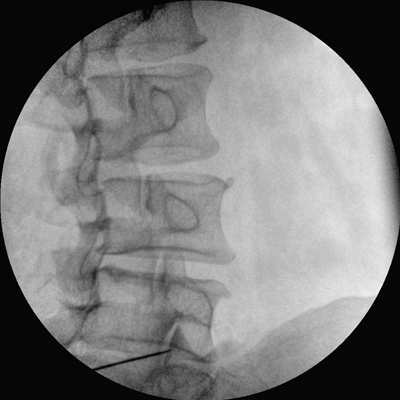

數(shù)字高清影像  助力臨床診斷

專業(yè)的圖像處理系統(tǒng),為您提供高分辨率、高灰階圖像。

Clinical picture

臨床圖片